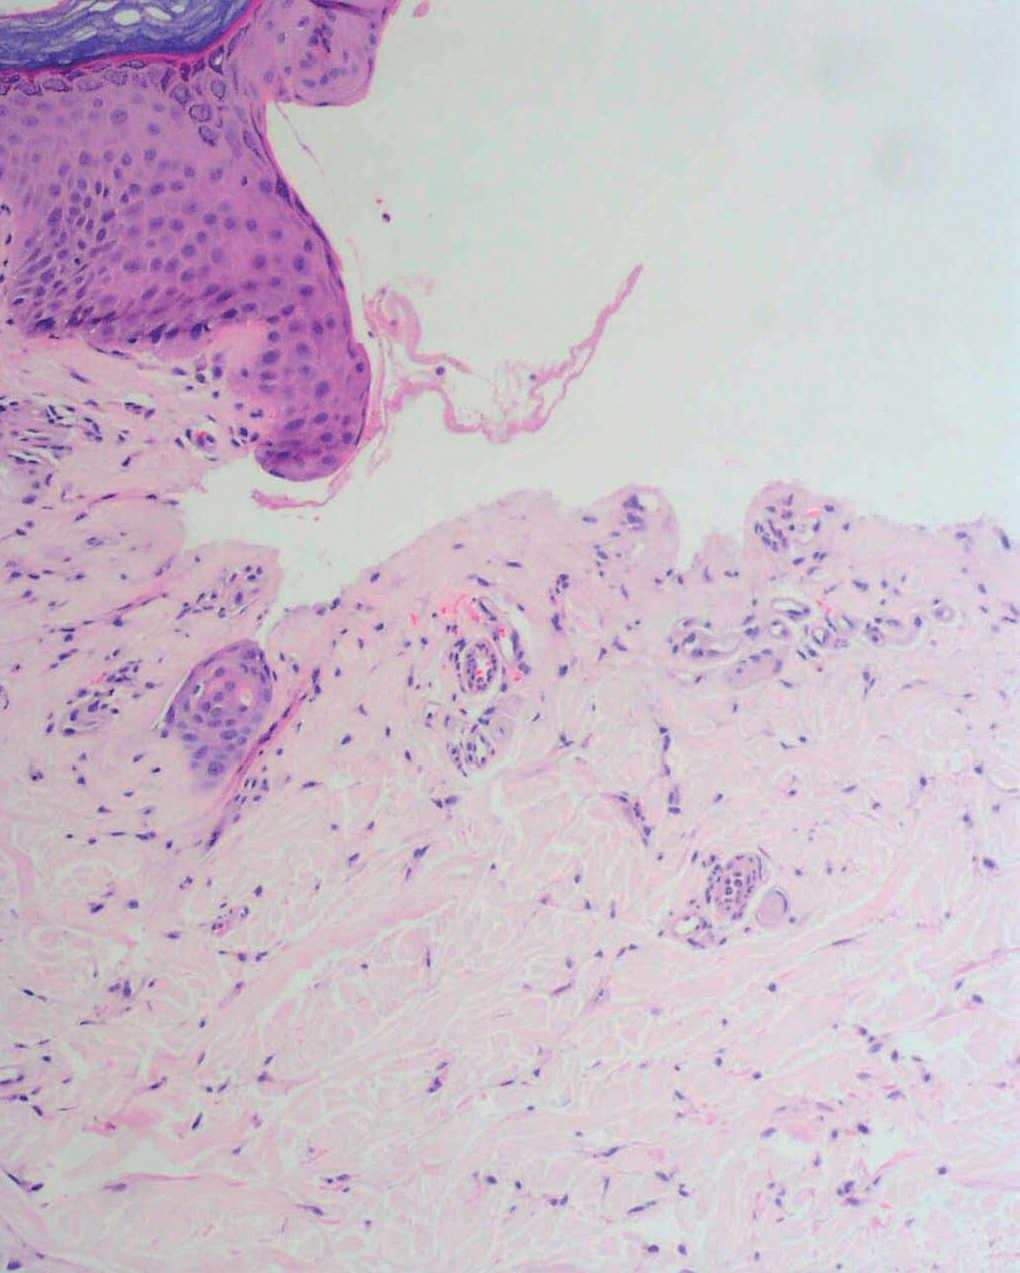

Fig. 2.--Ampolla subepidérmica sin infiltrado inflamatorio y con aspecto festoneado de las papilas dérmicas.

El estudio histopatológico mostró una ampolla subepidérmica con ausencia de infiltrado inflamatorio. La técnica de PAS reveló la presencia de anillos hialinos perivasculares.

El estudio histopatológico recuerda a una PCT con una ampolla subepidérmica y con un escaso infiltrado inflamatorio. Los vasos de la dermis muestran depósitos de un material PAS positivo. Con microscopia electrónica se observa una reduplicación de la membrana basal y un depósito perivascular de un material fibrilar fino 5.